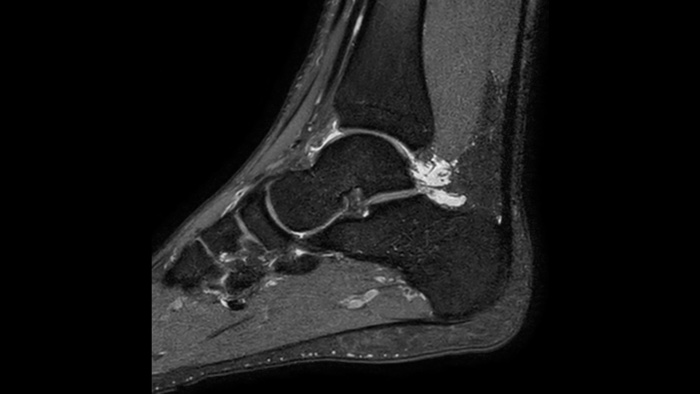

Ahora puede tenerlo todo con Ingenia Ambition. Ofrece la oportunidad de mejorar sus imágenes de resonancia magnética en todos los niveles.

Confianza diagnóstica Ofrece una resolución espacial hasta un 60% más alta en el mismo tiempo de escaneo. 4

Ahora puede tenerlo todo con Ingenia Ambition. Ofrece la oportunidad de mejorar sus imágenes de RM en todos los niveles.

Confianza diagnóstica Amplíe su capacidad de obtener imágenes excelentes en todas las áreas clínicas. Vea cómo se benefician sus compañeros.